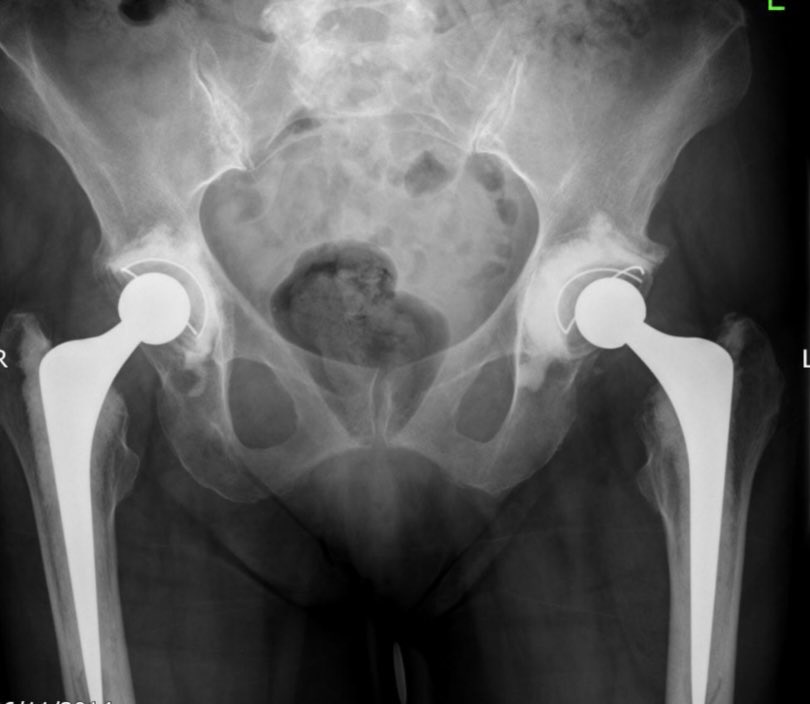

Patients might tolerate some lengthening and might tolerate some increase in offset. If you do both together, in the same hip, they’ll hate it. As people pointed out that was the case in this patient. https://twitter.com/exeterhipunit/status/1353473014525001728

So the socket wasn’t medicalised into the cemented mantle at primary. The cement is well fixed in all but zone 1 where there is a lucent line. That can be managed with in cement revision. Ream out poly cup, burr medial cement away and recement new cup

However, issues with that technique are that there is a risk of relateralising with the in cement revision and, if worried about instability, the options for increasing head size are limited. That’s a small socket.

So decision made to remove all of the cement, ream and insert uncemented shell with modular dual mobility for stability in view of reduced tension.